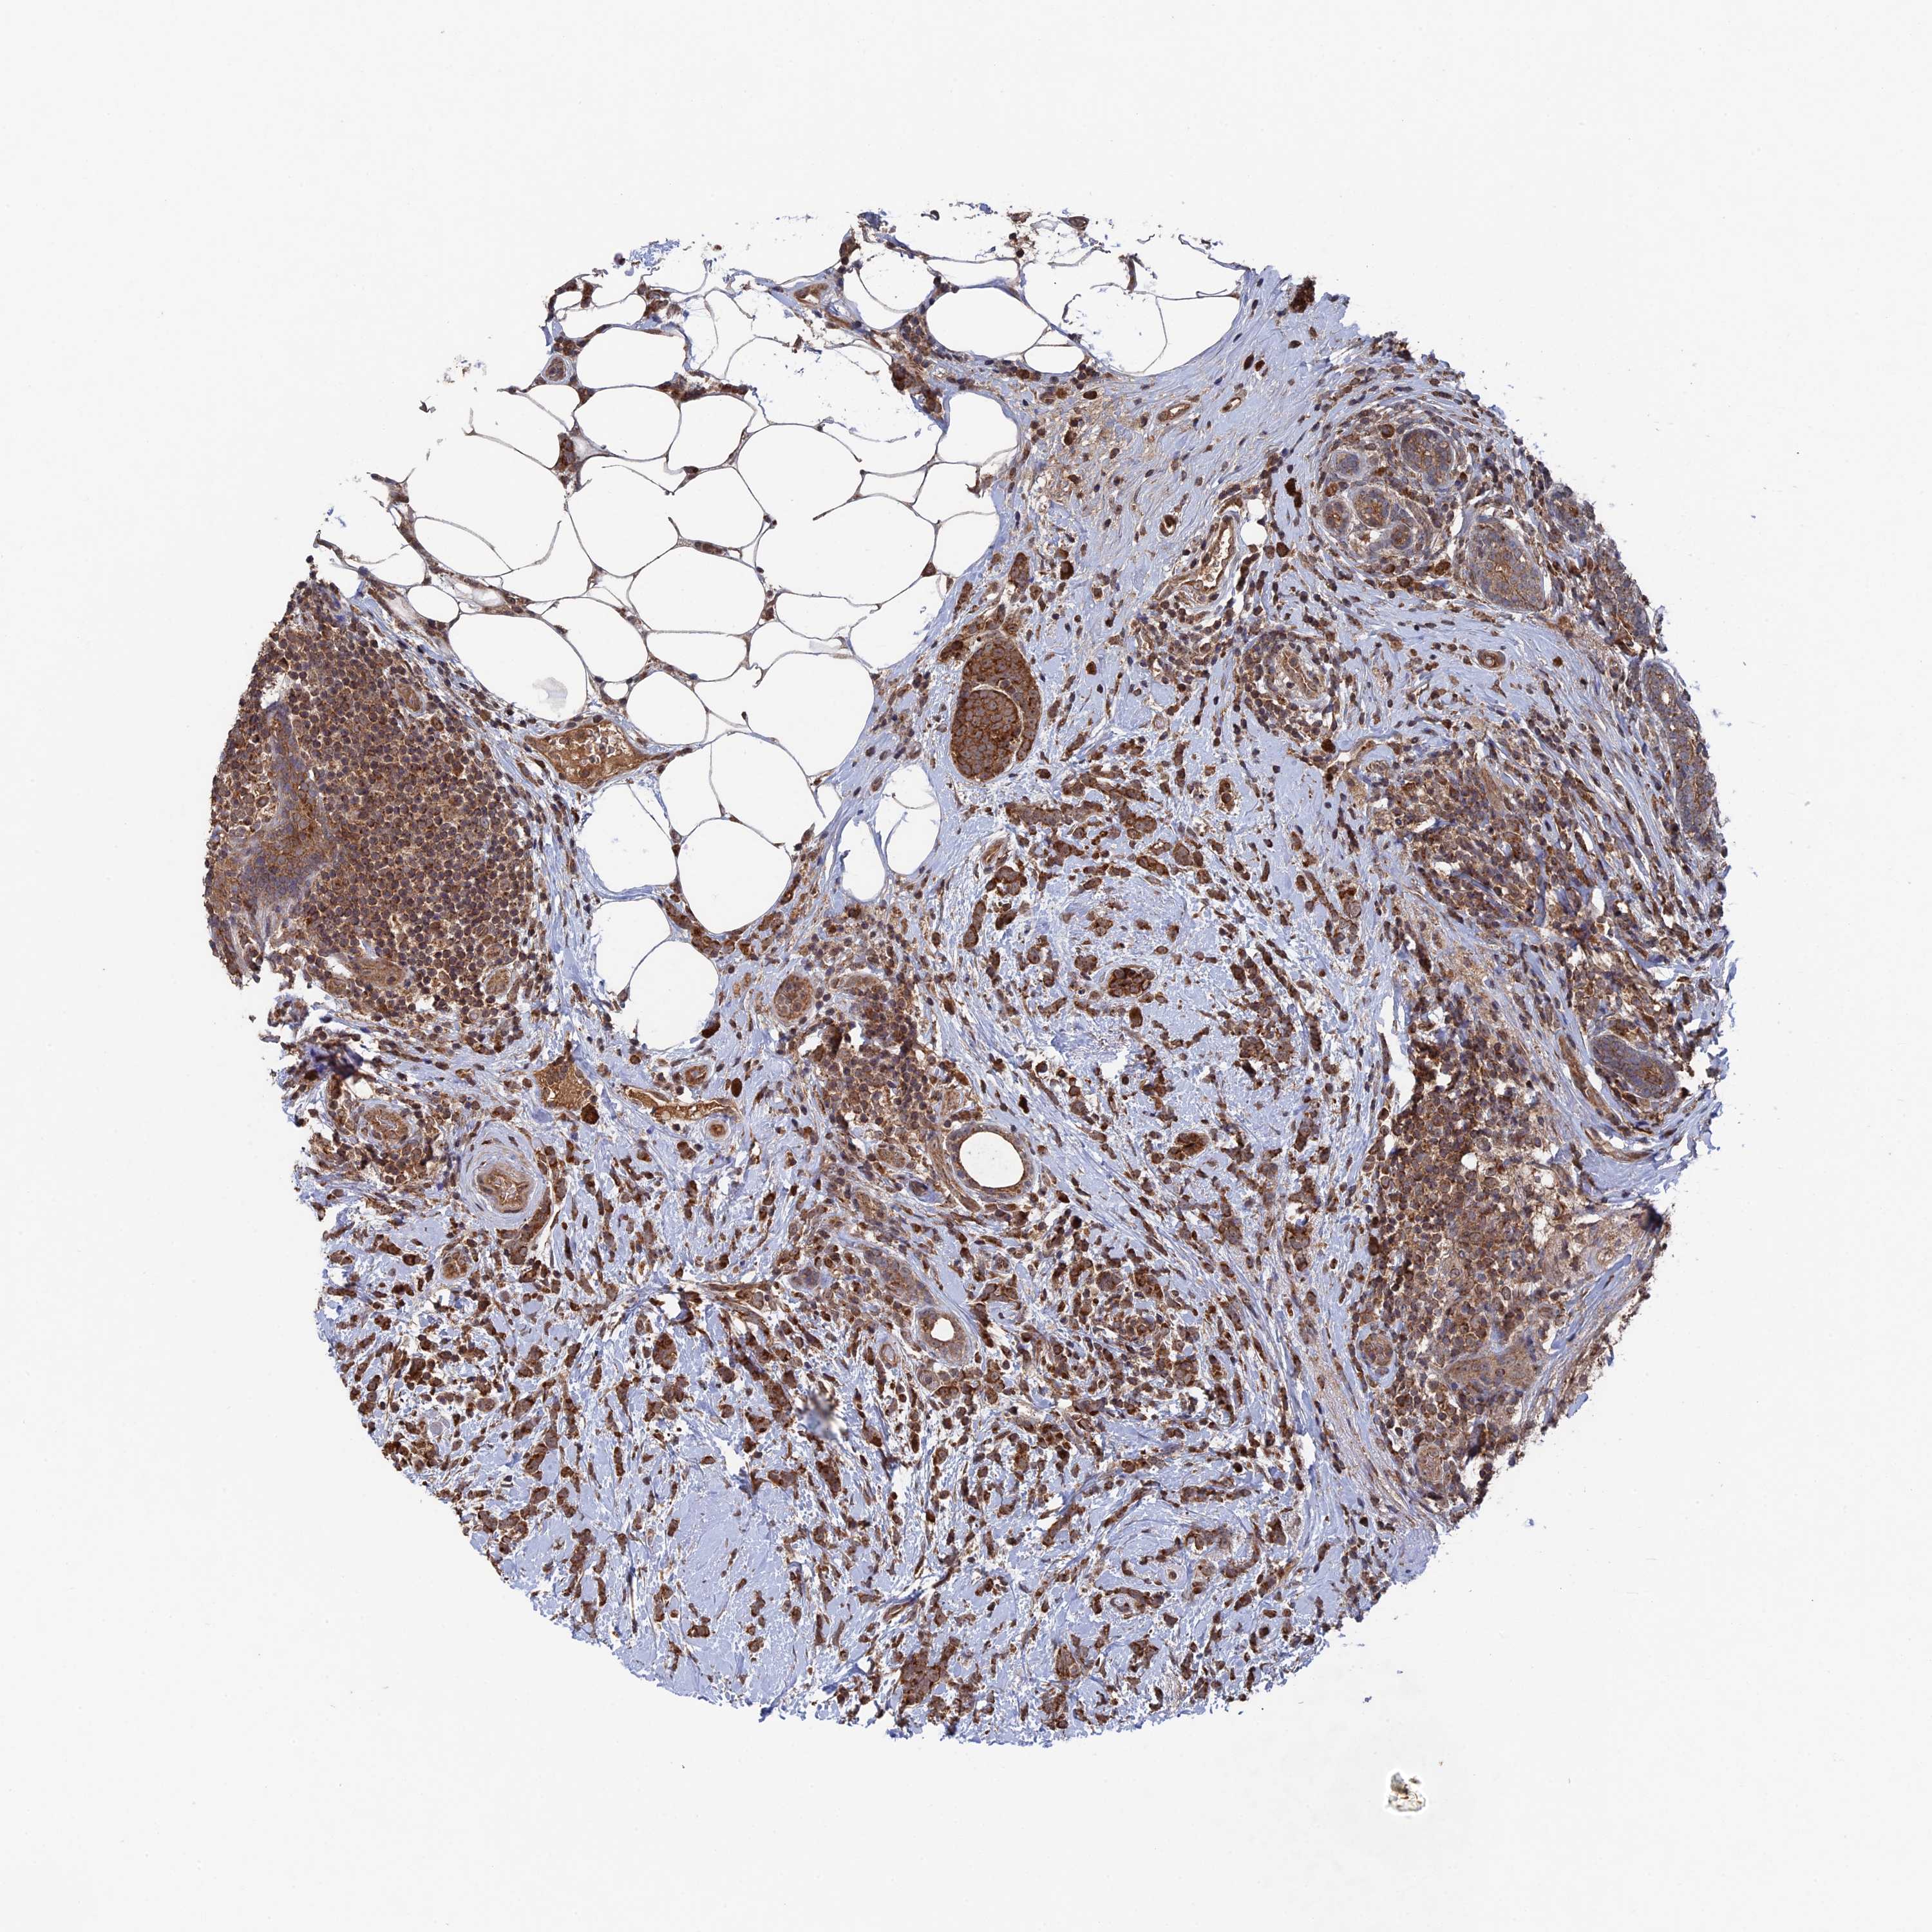

BRCA TCGA BRCA VALIDATION PROTEIN EXPRESSION